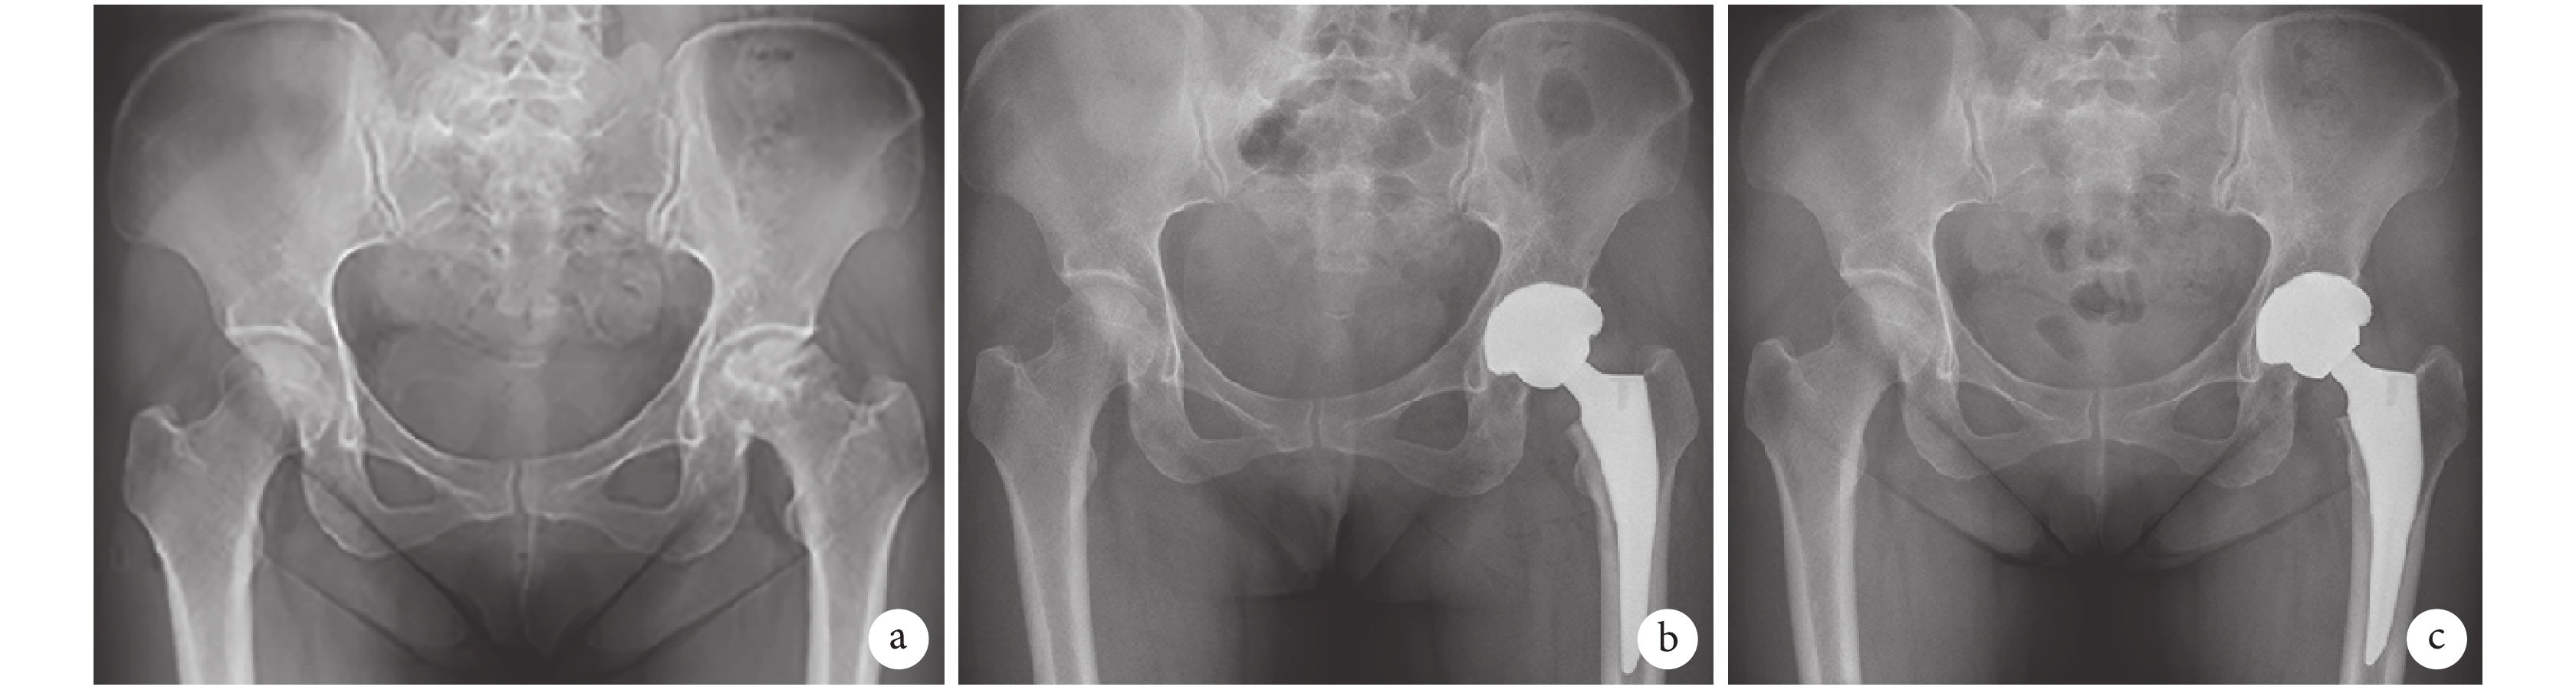

ESRD 組:住院期間出現心力衰竭加重 1 例,給予利尿、控制血壓、限制液體入量后病情好轉,出院至心內科門診繼續隨訪治療;肺部感染 1 例,急性上呼吸道感染 1 例,均經抗感染治療后痊愈;下肢深靜脈血栓形成 2 例,抗凝治療后痊愈;出院 20 d 后 1 例因出現切口淺表感染再次入院,給予引流、紅外線烤燈治療及切口換藥后痊愈。住院期間無死亡患者,隨訪期間透析患者死亡 2 例,分別為術后 3 年死于肺癌、術后 2.5 年死于肺部感染并發呼吸衰竭。對照組:住院期間出現肺部感染和下肢深靜脈血栓形成 1 例,經抗感染和抗凝治療后痊愈,無出院后 90 d 內再入院患者,隨訪期間無死亡患者。隨訪期間兩組患者均未出現假體松動及假體周圍感染,假體位置良好,假體周圍未見透光線。見圖 1。

a. 術前; b. 術后即刻;c. 術后 3.8 年

Figure1. X-ray films of 44-year-old female patient with left femoral head necrosis in ESRD groupa. Before operation; b. At immediate after operation; c. At 3.8 years after operation